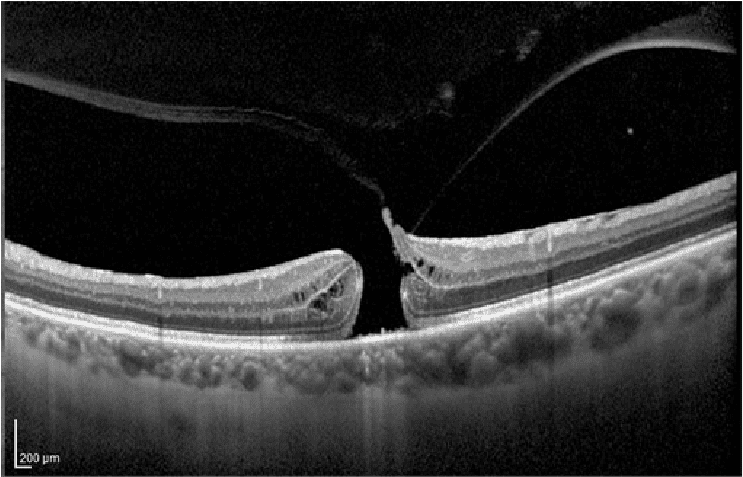

→ Tomografía de Coherencia Óptica u OCT Macular: con esta prueba determinamos el tamaño y la forma del agujero macular para observar el estado de las diferentes capas de la retina y descartar edema macular quístico.

→ Tomografia de coherencia óptica OCT de agujero macular completo.